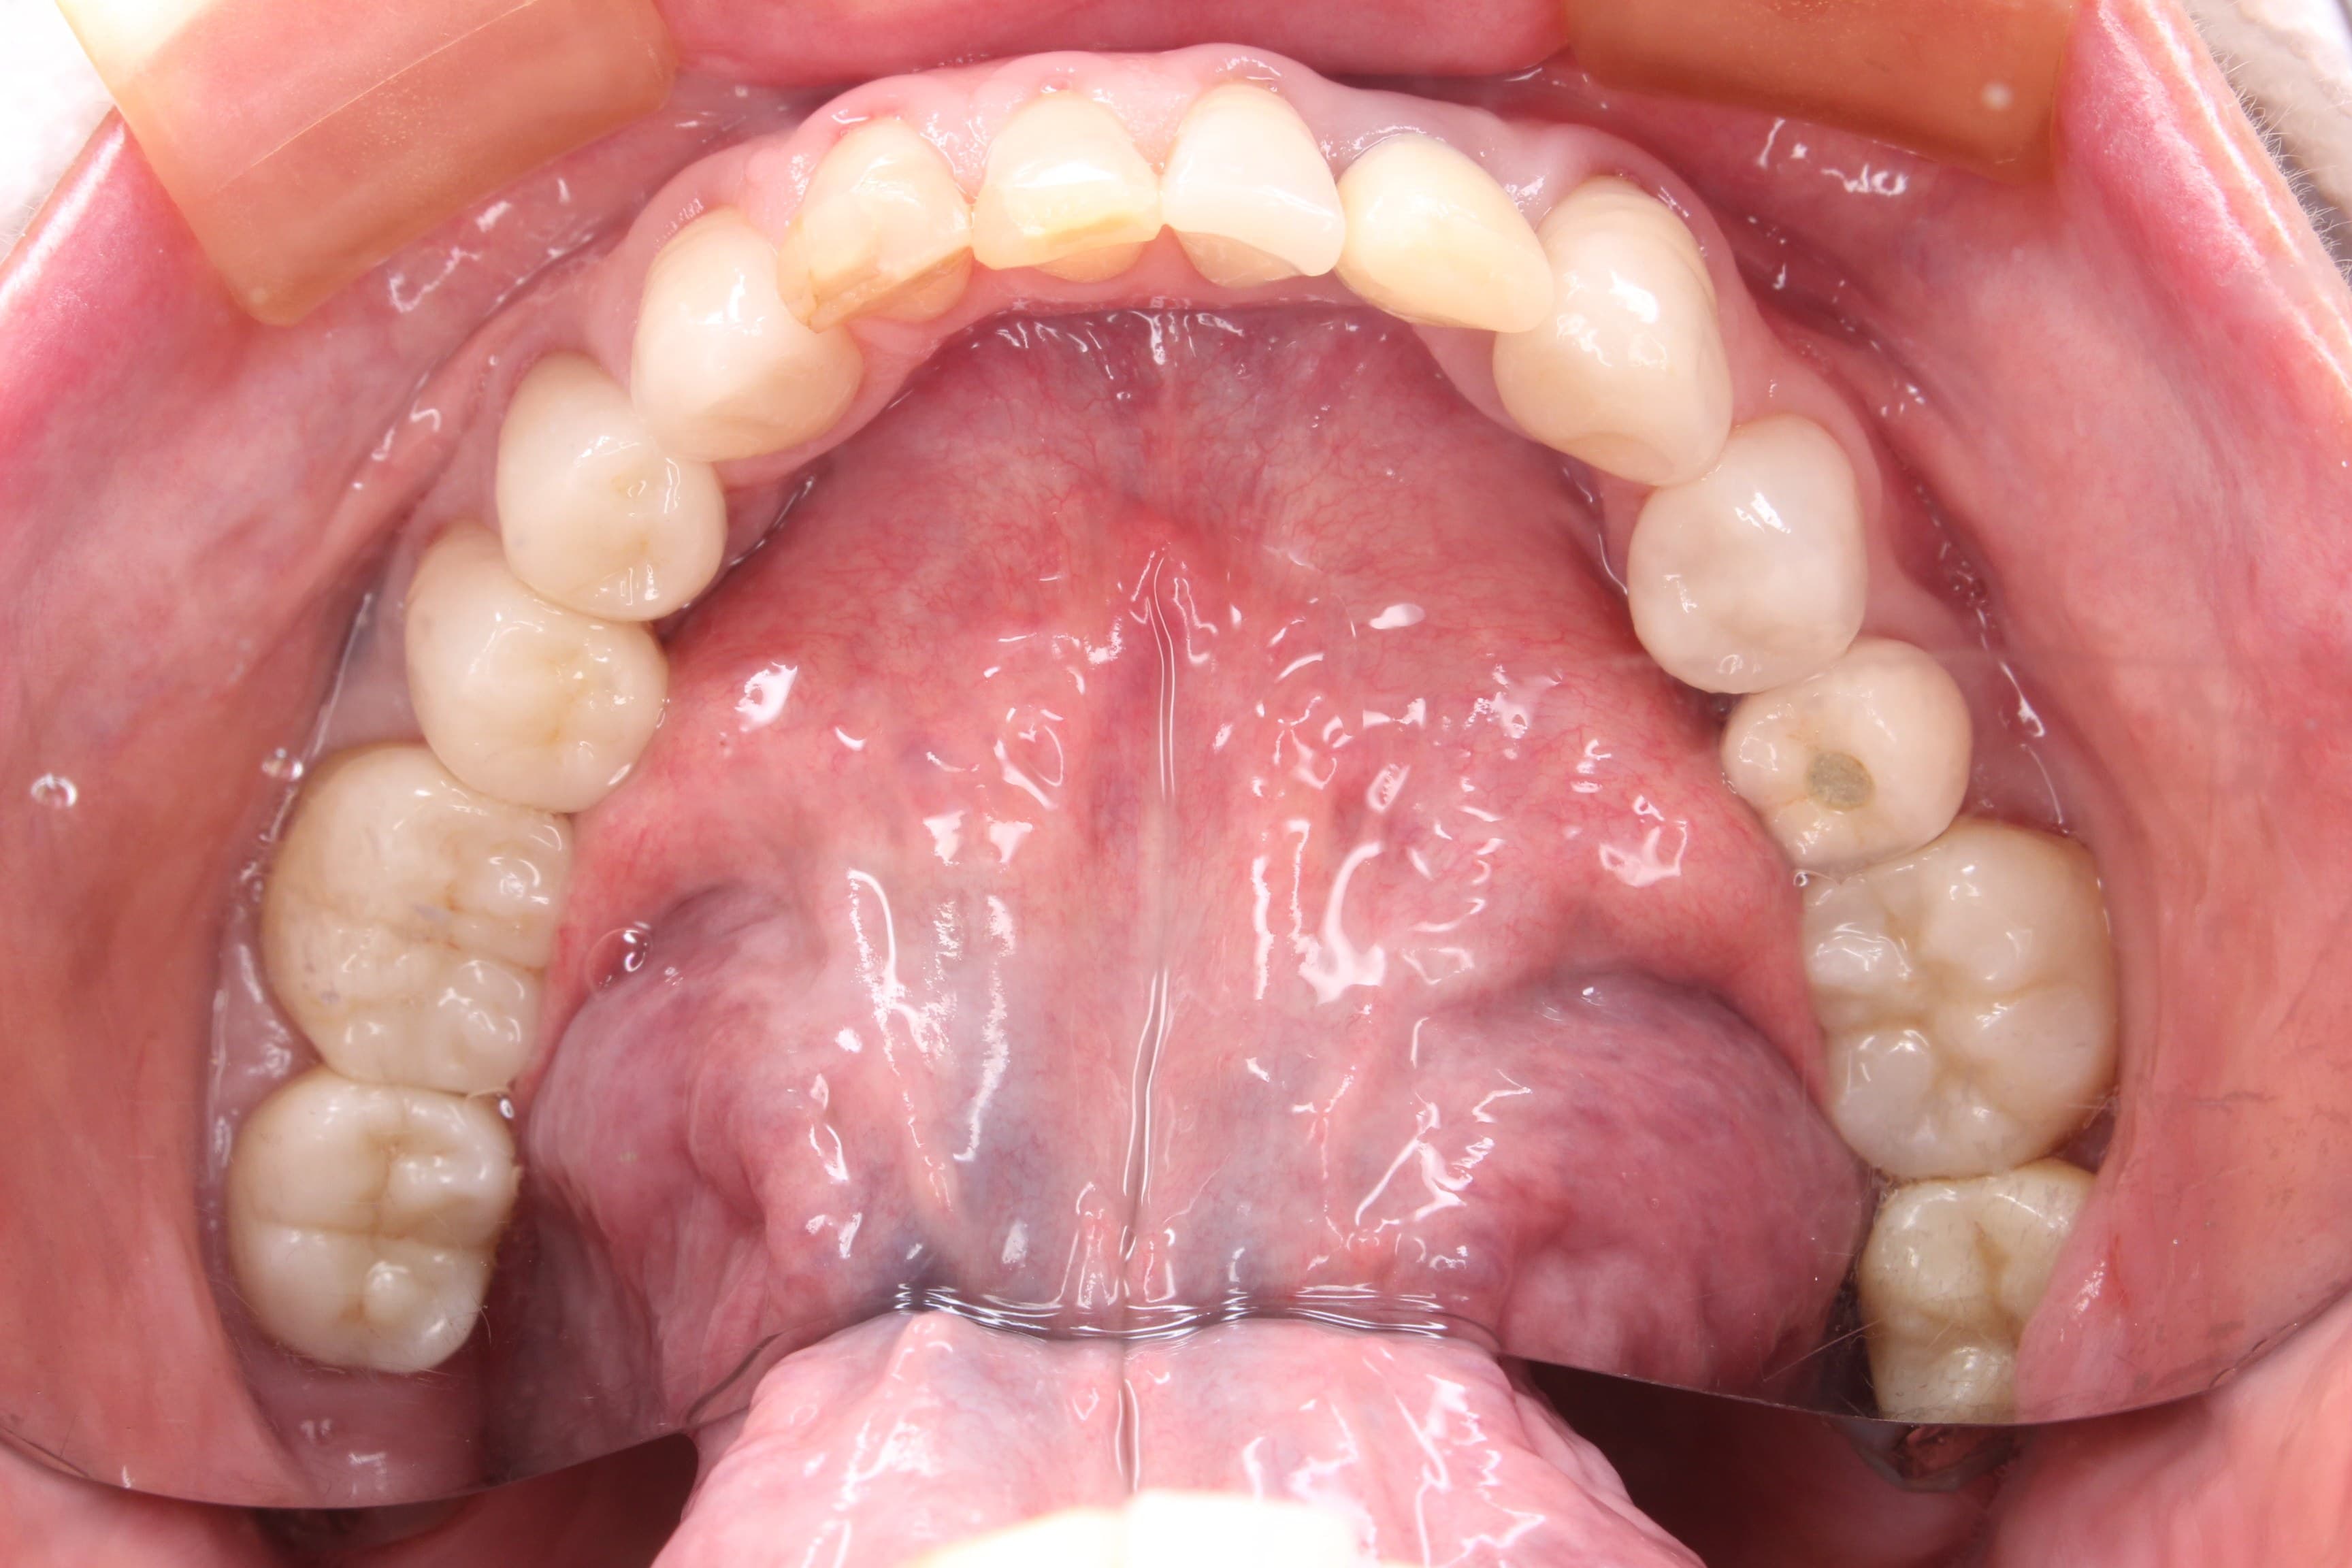

今回ご紹介するのは50代、女性の方です。

治療前の下顎

時々奥歯が痛くなるという理由で来院されて、歯周病と虫歯の問題が発覚しました。

全ての歯に何かしらの治療がされており、子供の頃から歯医者には頻繁に通っていたそうです。

部分的にセラミックなどの審美治療と思われる補綴物が入っていましたが、残念ながら二次虫歯や不適合で再治療が必要な状態です。

また口腔内の衛生状態もあまり良くなく、再発しやすい環境になっていました。